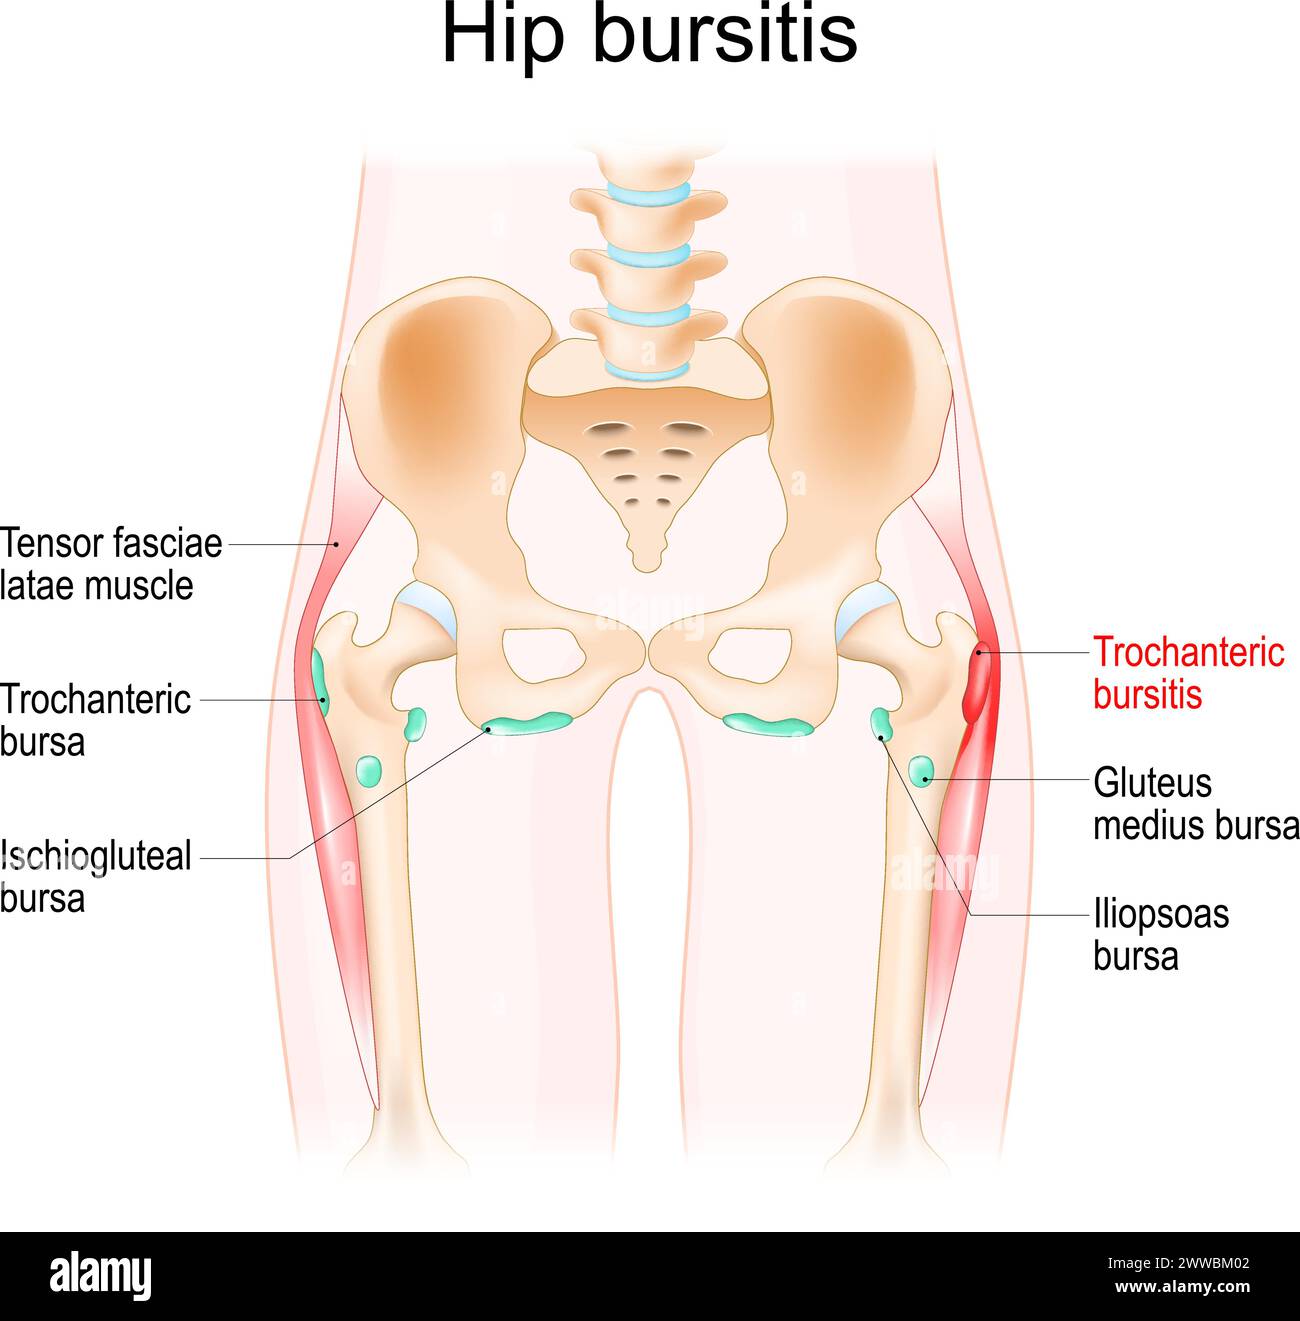

Hip bursitis. Muscles, Synovial bursas and bones of a human hip. Trochanteric bursitis. Realistic vector illustration Stock Vectorhttps://www.alamy.com/image-license-details/?v=1https://www.alamy.com/hip-bursitis-muscles-synovial-bursas-and-bones-of-a-human-hip-trochanteric-bursitis-realistic-vector-illustration-image600776066.html

Hip bursitis. Muscles, Synovial bursas and bones of a human hip. Trochanteric bursitis. Realistic vector illustration Stock Vectorhttps://www.alamy.com/image-license-details/?v=1https://www.alamy.com/hip-bursitis-muscles-synovial-bursas-and-bones-of-a-human-hip-trochanteric-bursitis-realistic-vector-illustration-image600776066.htmlRF2WWBM02–Hip bursitis. Muscles, Synovial bursas and bones of a human hip. Trochanteric bursitis. Realistic vector illustration